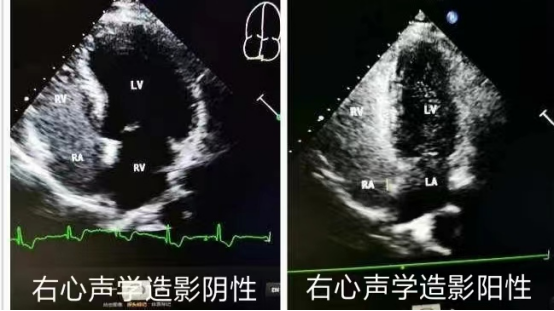

(3)右心声学造影